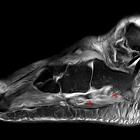

Ruptur der

Sehne des M. peroneus longus distal des Os peroneums in der MRT.